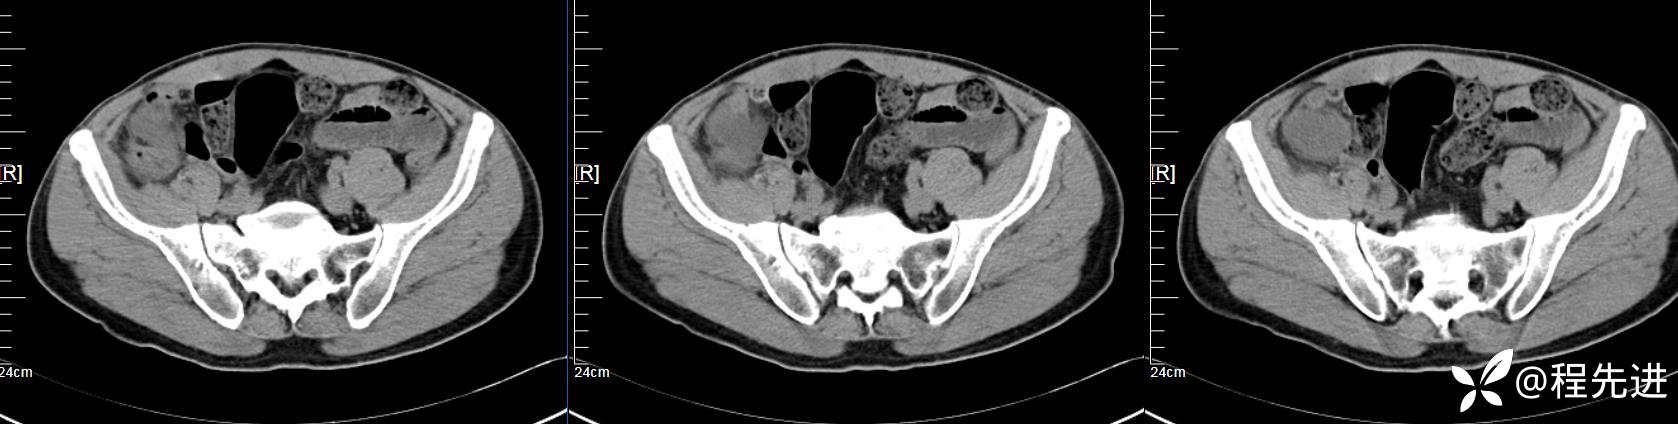

【患者信息】:男,61岁

【现病史及既往史】:右下腹部疼痛伴腹胀2天

【影像检查】